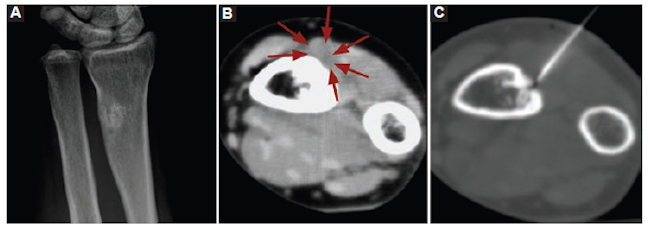

Mujer de 24 años que consultó por dolor continuo y progresivo en el antebrazo derecho de 8 años de evolución. En la exploración física no se hallaron masas palpables. La radiografía (Rx) evidenció esclerosis irregular en la diáfisis distal del radio derecho y la tomografía computada (TC) identificó un tejido de densidad de partes blandas adyacente. Si bien se consideró un posible origen traumático, entre los diagnósticos diferenciales se mencionaron también lesiones agresivas como el osteosarcoma perióstico, el osteosarcoma superficial y el condroma perióstico. Por consiguiente, se solicitó biopsia guiada por TC (Fig. 1).

El resultado de la biopsia fue tejido fibroconectivo y hueso compacto sin evidencia de células atípicas. Los resultados fueron interpretados por la clínica y radiológicamente como calcificación heterotópica y esclerosis ósea.